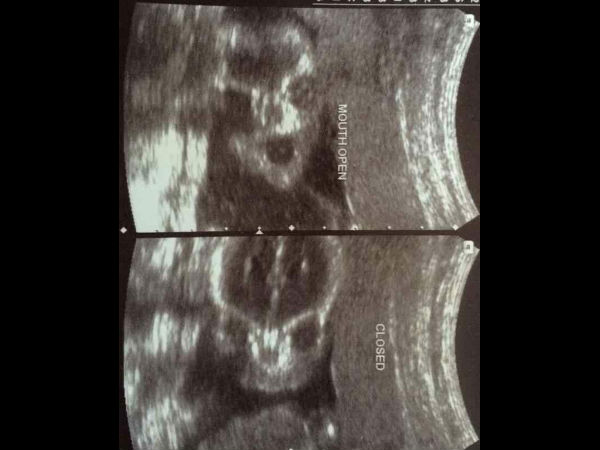

கர்ப்ப காலத்தில் தாயின் வயிற்றில் குழந்தைகளின் நிலை: ஸ்கேன் படங்கள்!

கர்ப்பத்தின் பொழுது ஸ்கேன் பரிசோதனை மிக முக்கியமானது; இந்த பதிப்பில் கர்ப்ப காலத்தில் எடுக்கப்படும் ஸ்கேன் படங்களில் குழந்தைகளின் நிலை பற்றி படித்து, புகைப்படங்களை பார்த்து அறிவோம்.

கர்ப்பத்தின் பொழுது ஸ்கேன் பரிசோதனை மிக முக்கியமானது; கர்ப்ப காலத்தில் தாயின் வயிற்றில் குழந்தைகளின் நிலை குறித்து அறிய வேண்டியது மிகவும் முக்கியம்; ஸ்கேன் படங்கள் மூலமும், ஸ்கேன் பரிசோதனை மூலமும் எளிதில் தாயின் வயிற்றில் வளரும் கருவின் நிலையை அறியலாம்.

குழந்தையின் நிலை என்று கூறும் பொழுது குழந்தையின் உடலில் ஏதேனும் ஆரோக்கிய சீர்கேடு இருந்தால் கூட, அதை கருவிலேயே கண்டு அறிந்து குணப்படுத்துவதற்கான வழிமுறைகளை அறியவும், முடிந்தால் அதனை கருவிலேயே குணப்படுத்தவும் கூட முயலலாம். இந்த பதிப்பில் கர்ப்ப காலத்தில் எடுக்கப்படும் ஸ்கேன் படங்களில் குழந்தைகளின் நிலை பற்றி படித்து, புகைப்படங்களை பார்த்து அறிவோம்.

பின் 15வது வாரம் வரையில் ஒரு விதை வடிவ மூட்டை போன்ற குழந்தையையே காண முடியும். ஆனால், 27 முதல் 28 ஆம் வாரத்தில் குழந்தையின் முழு வளர்ச்சியை அதாவது முழுமையான உருவாக்கம் பெற்ற குழந்தையை மிகவும் தெளிவாக தாயின் வயிற்றில் காண முடியும். இந்த கண் கொள்ளா காட்சியை காட்ட கர்ப்ப கால ஸ்கேன் பரிசோதனை மிகவும் உதவுகிறது.

குழந்தை தாயின் கர்ப்ப காலத்தில் உருவான பின் முதன் முதலாக ஸ்கேன் பரிசோதனை மூலம் குழந்தையின் இருப்பிடத்தை மட்டுமே காண முடியும். பின்னர் ஒரு சில வாரங்களுக்கு பின் குழந்தையின் இதய துடிப்பை கேட்டு அறிய முடியும். இதன் பிறகு குழந்தைகளின் தலை மற்றும் தலையின் அமைப்புகள், உடலின் வடிவம் மற்றும் குழந்தை உள்ள அம்னியாட்டிக் சாக் போன்ற உறைகள் இவற்றையும் ஸ்கேன் பரிசோதனை மூலம் காண முடியும்.